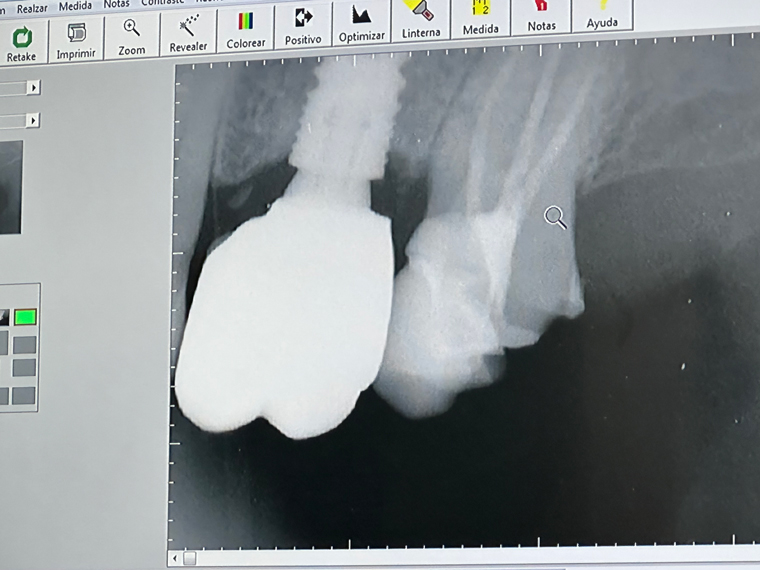

I was biting into something hard and all of the sudden I had a small piece of tooth in my hand. By feeling around in my mouth, I could tell that it was the back molar on the left-hand side. I was afraid that it was an implant and so I immediately made an appointment to check it out. Dr. Alejandro Barron at Dental Studio by Pedro Ortiz quickly took an Xray of the teeth and gave me the good and bad news. The good news was that it was not an implant. The bad news was it was a crown on the back molar. Luckily, the Xray confirmed that this tooth had a root canal and so I was in no pain.